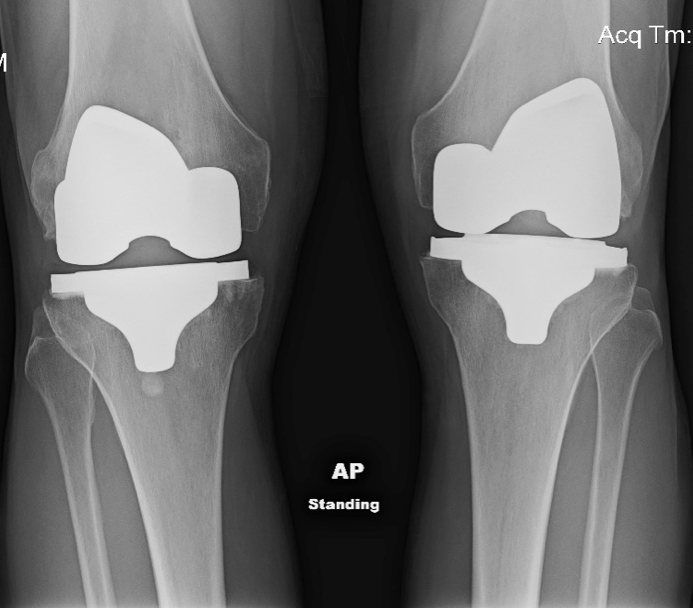

From www.sciencephoto.com

Total knee replacement, Xrays Stock Image C047/2771 Science Press Fit Knee Replacement Video See what happens during knee replacement surgery in this video and learn about the. Matthew harb specializes in minimally invasive, muscle sparing, hip and knee replacement surgery. Robotic cementless (press fit) total knee replacement. This cementless knee system is fda approved for use with the mako robot, combining two of the most recent knee joint replacement advancements into one cutting. Press Fit Knee Replacement Video.